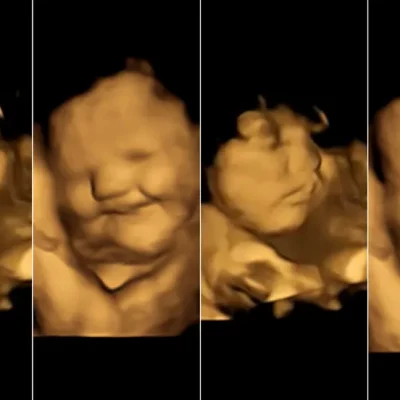

Bebês reagem a sabores de alimentos com expressões faciais ainda na barriga da mãe, mostra estudo inédito

Para os pesquisadores, os resultados obtidos com ultrassom 4D na fase final da gestação podem contribuir para informar as mães sobre a importância de uma alimentação saudável durante o período.